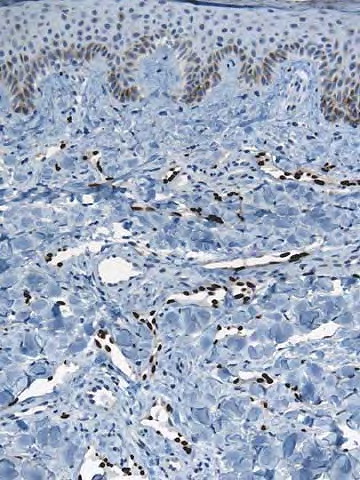

Histogenesis

The histogenetic derivation of the KS tumor cells (i.e., the cells lining the irregular vascular-like spaces of early and angiomatous lesions and the cells composing the bundles and interlacing fascicles of solid tumors) has been the subject of intense research over the past two decades. The immunophenotype of these cells (i.e., vWF+/-, PAL-E-, CD31+, CD34-, VEGFR3+) characterizes them as part of the lymphatic endothelial differentiation lineage.29,30 The recent demonstration that HHV-8 replicates better in lymphatic than in blood vascular endothelial cells is a further argument for this assumption.31 However, the finding that infection of blood vascular endothelial cells with HHV-8 leads to a phenotypic switch towards lymphatic endothelial cells31,32 leaves the possibility that an immature angioblast either resident in the skin or circulating and able to differentiate into both endothelial cell lineages is the initial precursor of KS tumor cells.33,34